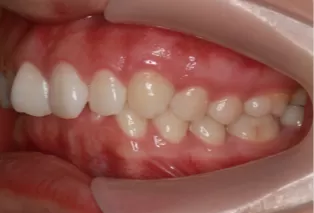

Photos intra-orales